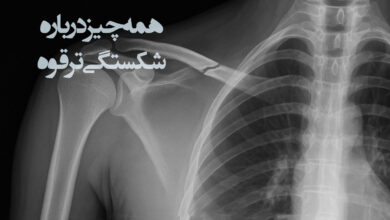

روش های تشخیص و درمان شکستگی ترقوه

شکستگی ترقوه یک آسیب شایع اما قابل درمان است که بیشتر بر اثر ضربه مستقیم به شانه، زمین خوردن یا…